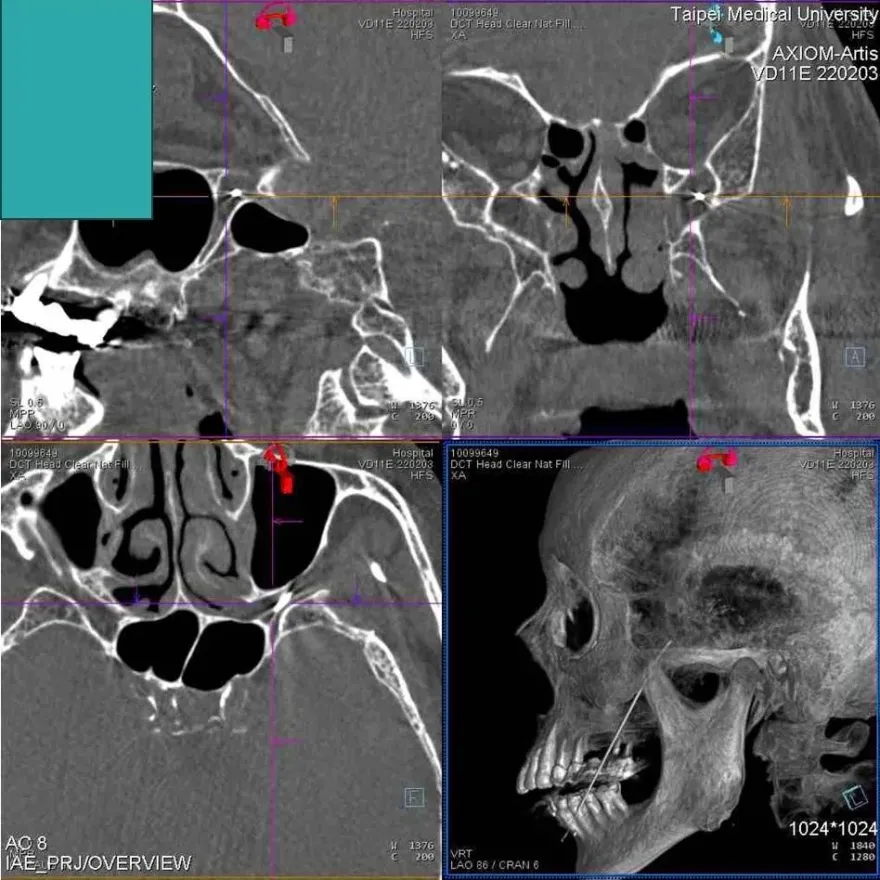

三叉神經痛

顏面神經

顏面神經失調

雙和醫院